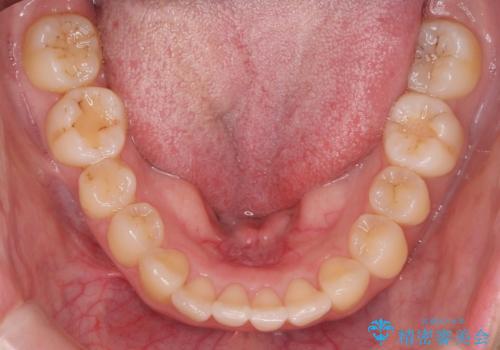

- 前歯のがたつきを主訴に来院。

前歯は目立つのでワイヤー矯正は絶対にしたくないとのことでした。

右上の奥歯を後ろに送り、前歯が出っ歯にならないように並べました。

また、右下の奥歯に一部目立たないように部分的なワイヤー矯正を行い、右下の奥歯が反対咬合になっていたのもしっかり中に入れて治療しています。

奥歯の反対咬合を治すのはインビザラインではかなり難しいのですが、しっかり治療できました。